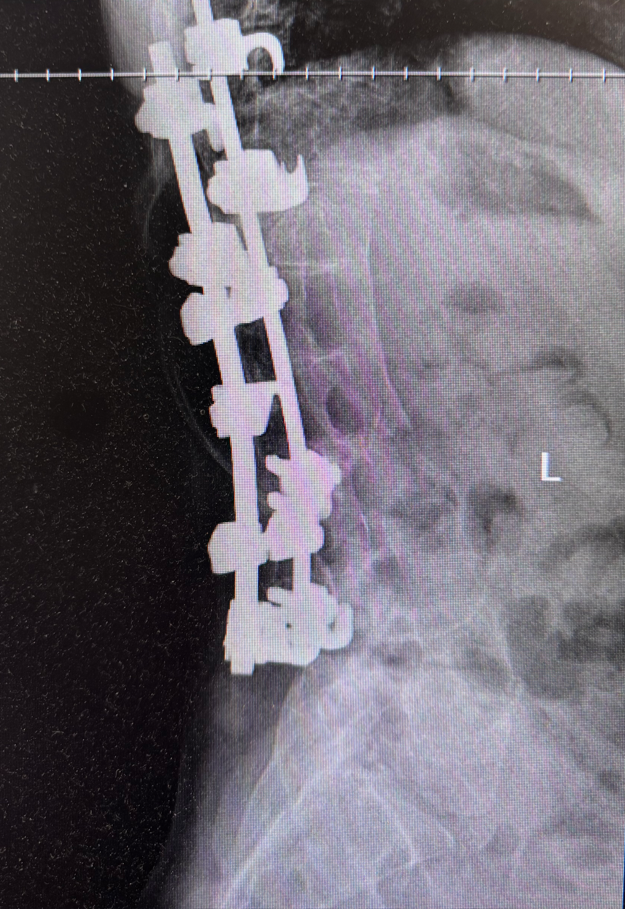

After two years of bracing, my scoliosis progressed to an 81-degree curve and started affecting my breathing and my way of life. By 1993, Dr. Dunham said we needed to really think about surgery. I remember being excited because I had never had surgery and it sounded cool, and I was also ready to be out of that sweat inducing brace. I credit my dad with being cool as can be while on the inside having no clue what the future held. His demeanor and his breezy attitude towards getting me ready for this new surgery gave me a confidence and excitedness that I didn’t expect. The date was set. March 22, 1993. This shaped up to be quite a month and year for me! Not only did we schedule a surgery that would be new to the dr. and new to me, we ALSO had the crazy Blizzard of 1993 the second week of March in Birmingham, AL. We had to watch the weather and pray it would come and go fast so we could not only have our power restored but also make my surgery!

Luckily, it cleared up and life got back to normal. By life, I mean sports for my younger siblings and me getting all assignments I may need ahead of time. At one of the soccer games for a sibling, by dad took a spill down a steep hill carrying a cooler to the players and cracked a couple of ribs. My surgery was scheduled to be done two days later. We showed up to the hospital the night before and I was prepped and ready the next day. I remember the dr letting me see some of the tools he would use. I guess my face said it all because I remember I immediately got the “count backwards” request and I was out. My next memory was seeing my cousin Michele (closest thing to a big sister to me). I had a weird feeling that I couldn’t describe, but it was an extreme need to go swimming right away. I guess they gave me the strong stuff! My poor dad had to sleep on that hospital cot that week with cracked ribs! I remember waking up in the middle of the night and he would have to leave the room so I could have a nurse come in and use the female urinal since I couldn’t get up out of bed yet. He was such a good sport because I KNOW that was painful for him to move so much! After 9 days in the hospital, I was allowed to learn how to sit up and walk with my new hardware. IT HURT SO BAD! When I was able to lay back down, I felt like the new rods had popped out of place and were sitting on the outside of my sewn up back. I remember my favorite nurse Pearl sneaking me her potato soup as a break from the hospital food, my dad sneaking the Nintendo in for me to play and all my classmates coming to see me.